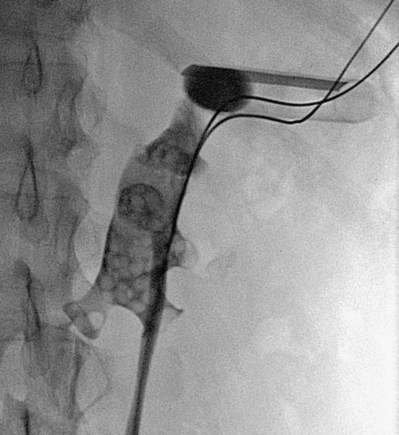

), and a guidewire can be passed from below and grasped by the nephroscope to establish through-and-through access from the external urethral meatus to the percutaneous entry site. A dual-lumen catheter can be placed as well. The small caliber of either catheter, however, does not provide much outflow from the kidney and may not prevent stone or tumor fragments from passing into the ureter along the catheter. A ureteral occlusion balloon catheter, which incorporates an approximately 15-Fr spherical balloon on the distal tip, more consistently prevents material from migrating down the ureter. The balloon should be carefully inflated in the renal pelvis, making sure the balloon is not in the ureter—which could lead to ureteral rupture—and then gently pull down to occlude the ureteropelvic junction (Fig. 47–12). Another alternative is to place a ureteral access sheath (usually 11 to 15 Fr) over a retrograde-inserted guidewire (Landman et al, 2003). The large outer diameter of the sheath effectively prevents particles from passing around the sheath into the ureter, and the large inner diameter affords excellent outflow of small stone particles. The disadvantages of employing a ureteral access sheath include the potential ureteral trauma from passing such a large device into the ureter and clogging of the catheter lumen by oversized stone fragments.

Figure 47–12 Occlusion balloon inflated and snugged down at ureteropelvic junction of contrast-filled upper tract collecting system.